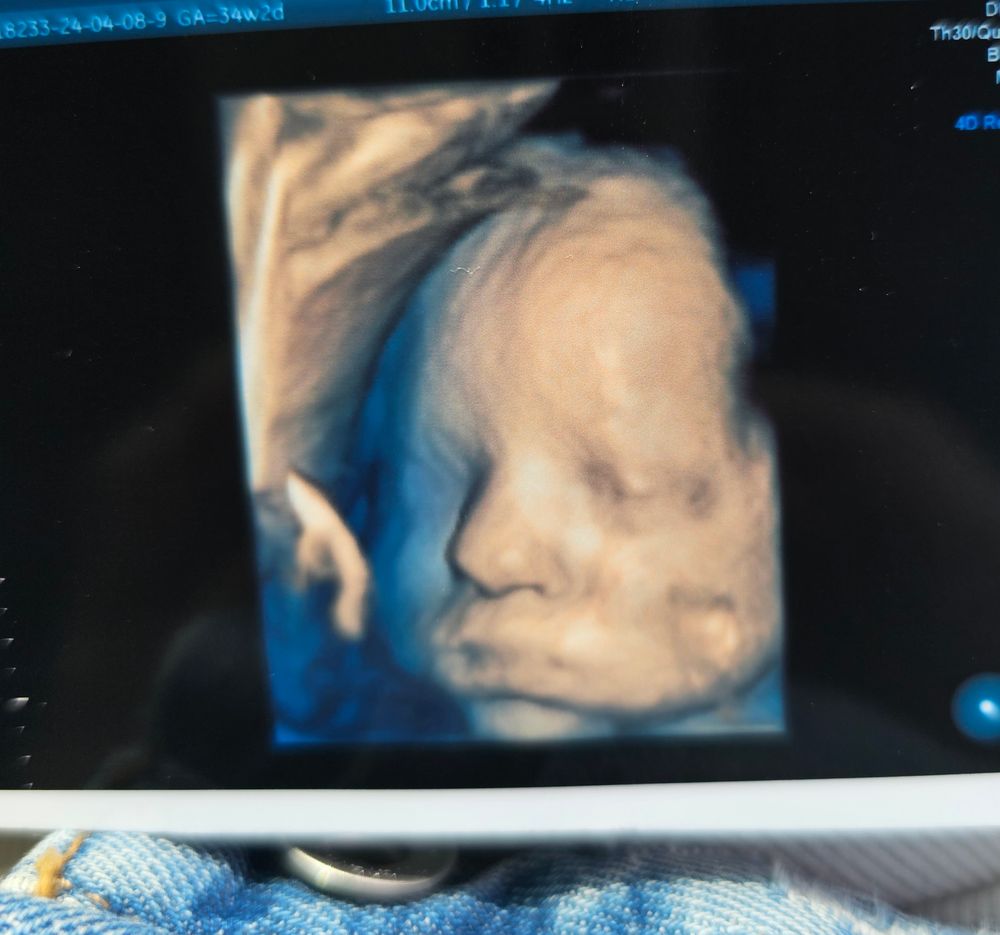

Девочки, по сроку 34.2 нед. Вес плода сегодня 2.050гр. А 2 недели назад был 1700гр, по узи и анализам все всегда в норме. Узистка сказала ,по нижней границе нормы вес. Старших рожала: на 42 нед 3150, и в 38 нед 2800. Переживаю теперь🙄